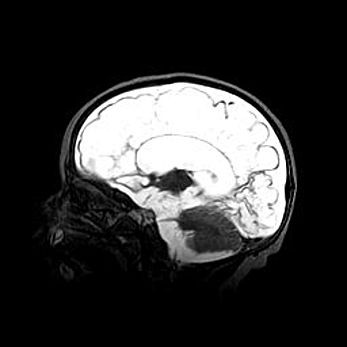

Церебральная ишемия II.

Возраст: 5 дней

Вес: 3400 г

Пол: женский

Окружность головы: 35 см

Срок гестации: 39 недель

Церебральная ишемия – это заболевание, характеризующееся недостаточностью (гипоксией) либо полным прекращением (аноксией) снабжения мозга кислородом по причине закупорки одного или нескольких сосудов. Это приводит к  что метаболическим расстройствам различной степени тяжести в тканях головного мозга, развитию коагуляционных некрозов и гибели нейронов.